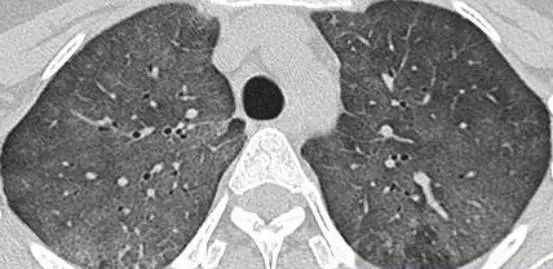

外源性過敏性肺泡炎肺部影像

為尋求進一步診治,張先生來到了我院。呼吸與危重癥醫(yī)學科宋剛主任詳細審閱了張先生的肺部CT片和相關檢驗報告,并詢問了接觸史,最終確診張先生患有外源性過敏性肺泡炎。

外源性過敏性肺泡炎(HP),也稱過敏性肺炎,是一種由反復吸入某些具有抗原性的有機粉塵所引起的過敏性肺部炎癥。過敏性肺炎比較明顯的特征就是間質性肺炎、肉芽腫、細支氣管炎,其癥狀包括咳嗽、咳痰、呼吸困難、發(fā)熱、乏力和胸痛等,影像學表現(xiàn)為彌漫性肺部改變,以中上肺葉為主。